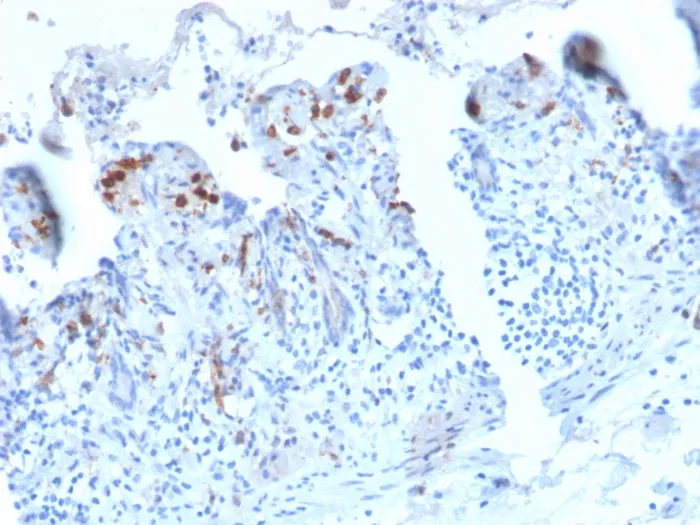

DC-SIGN is a transmembrane receptor that is expressed on the surface of dendritic cells and macrophages. It is involved in the innate immune system and recognizes numerous evolutionarily divergent pathogens ranging from parasites to viruses. The protein is organized into three distinct domains: an N-terminal transmembrane domain, a tandem-repeat neck domain and C-type lectin carbohydrate recognition domain. The extracellular region consisting of the C-type lectin and neck domains has a dual function as a pathogen recognition receptor and a cell adhesion receptor by binding carbohydrate ligands on the surface of microbes and endogenous cells. The neck region is important for homo-oligomerization, which allows the receptor to bind multivalent ligands with high avidity. Primary antibodies are available purified, or with a selection of fluorescent CF® Dyes and other labels. CF® Dyes offer exceptional brightness and photostability. Note: Conjugates of blue fluorescent dyes like CF®405S and CF®405M are not recommended for detecting low abundance targets, because blue dyes have lower fluorescence and can give higher non-specific background than other dye colors.Synonyms:

IHC, FFPE (verified)Validated Applications:

IHC, FFPEPositive Control:

THP-1 or HeLa cells (IF/FACS). Human liver or spleen lysate (WB). Human small intestine (IHC).Concentration: